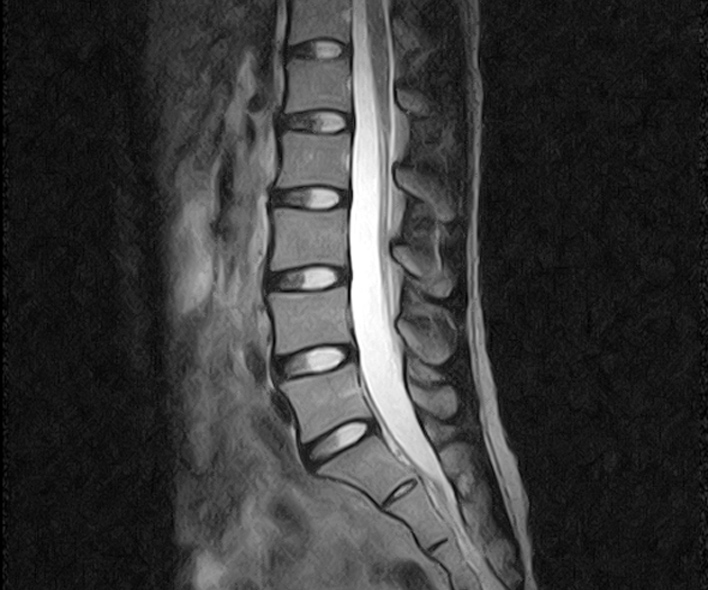

MRIで撮った画像とMRIで分かる疾患の例

腰椎

- 椎間板ヘルニア

- 腰椎圧迫骨折

- 脊柱管狭窄症 などの症状